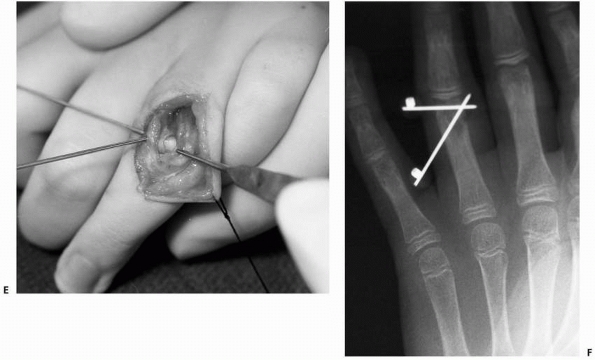

![]() |

FIGURE 8-33 (continued) C. Dorsal exposure revealed ulnar condyle outside of joint requiring incision of extensor tendon for reduction. D. Reduction of joint surface and Kirschner-wire fixation. E. Postoperative anteroposterior radiograph shows restoration of articular surface. F. Lateral radiograph shows sagittal alignment of condyles. (Courtesy of Shriners Hospitals for Children, Philadelphia, PA.)